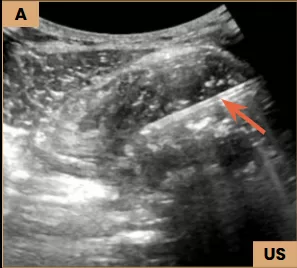

Image A: Ultrasound-guided biopsy using a Tru-Cut needle (arrow) obtained multiple soft tissue cores.